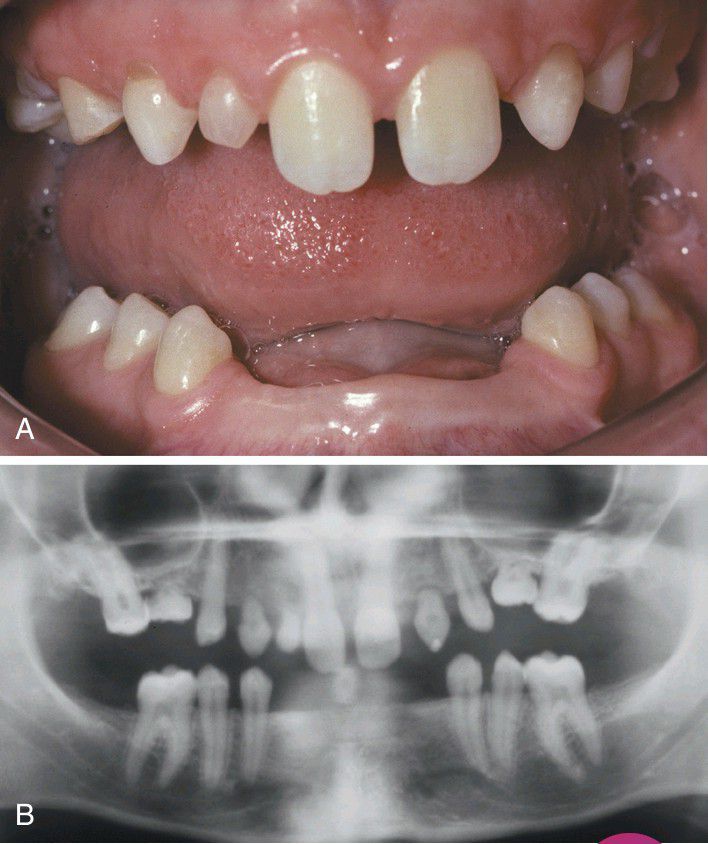

Hypodontia

Multiple developmentally missing permanent teeth and several retained deciduous teeth in a female adult. B, The panoramic radiograph shows no unerupted teeth in either jaw